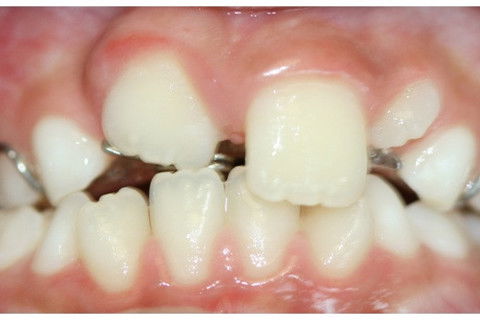

Ao exame clínico observou-se persistência do dente decíduo e erupção ectópica por palatina do sucessor permanente.

Foi realizada a exodontia do dente 51. Observa-se o dente 11 irrompendo por palatina, necessitando de tratamento ortodôntico.